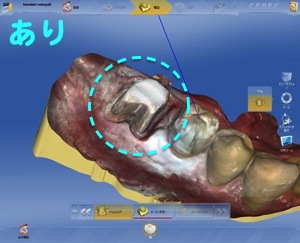

3ヶ月過ぎから仮歯を装着します。1ヶ月間使っていた後、最終の型取りに入ります。

施術から4ヶ月後、無事にセラミックで仕上げたインプラントが完成いたしました。